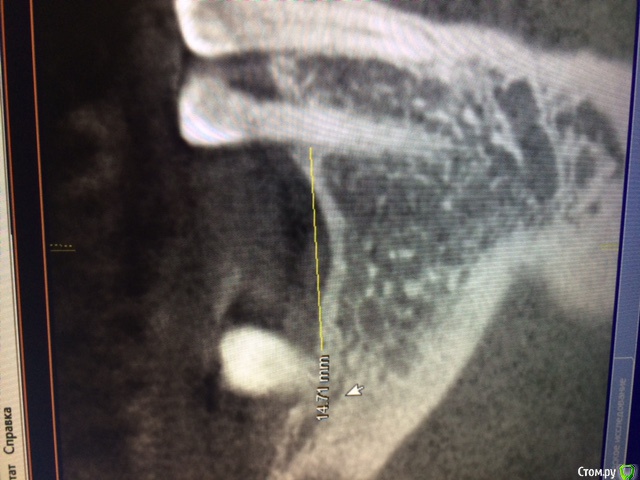

Аслан Опубликовано 24 января, 2015 Поделиться Опубликовано 24 января, 2015 Для начала лучше правильно заливать фотки. Не всем удобно вертеть монитор компа.Ситуация банальная. Их обсуждалось много уже. Нкр (апатос в перемешку с ауто, имплантация. Хотите - одномоментно, хотите раздельно. 1 Ссылка на комментарий